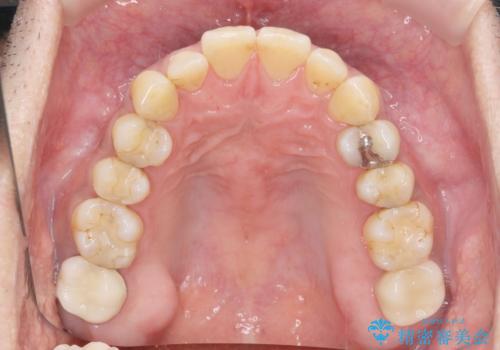

歯ぎしり いびきに効果的なスプリントナイトガード

歯ぎしりが気になる。